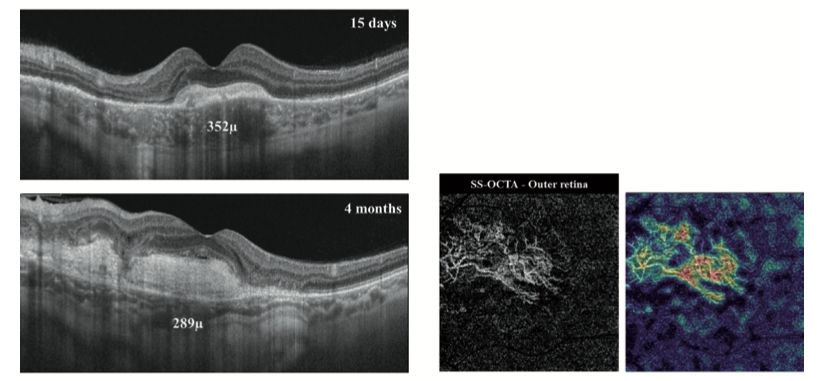

上图左:在随访期间进行左眼SS-OCT径向扫描,显示神经感觉层脱离以及先前提到的视网膜下病变的消退。右图:在4个月的随访中,SS-OCTA图像和6×6 mm视野中相应的视网膜外侧血流密度图显示了与新生血管复合物中高血流相对应的高强度信号。病变内大量成熟的大血管意味着主要是无活性的脉络膜新生血管(CNV)复合体。